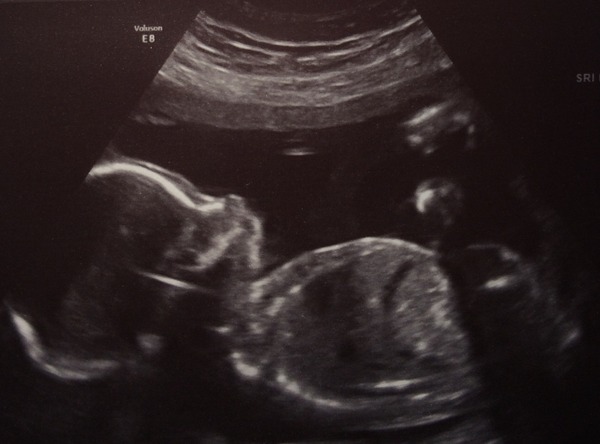

catnip85 · 19/12/2014 14:48

How did the scan go wantto? Its a little girl for me :) I'm absolutely over the moon

Hi ladies, good to see some new members! Scans are looking great Smile Congratulations on your little princess catnip!

Im 20 weeks now, got scan next Friday! Already know we are having a boy and have picked a name so it's all starting to feel real!